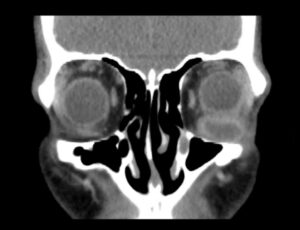

Inferior Rectus Abscess CT Coronal Unannotated. JETem 2025